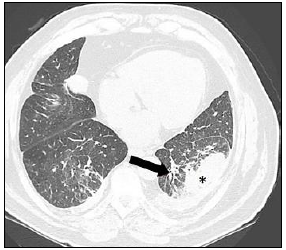

Observe a imagem radiológica que apresenta um achado demarcado pela seta e pelo asterisco:

Enunciado 913329-1

Assinale a alternativa correta sobre o exame apresentado anteriormente.